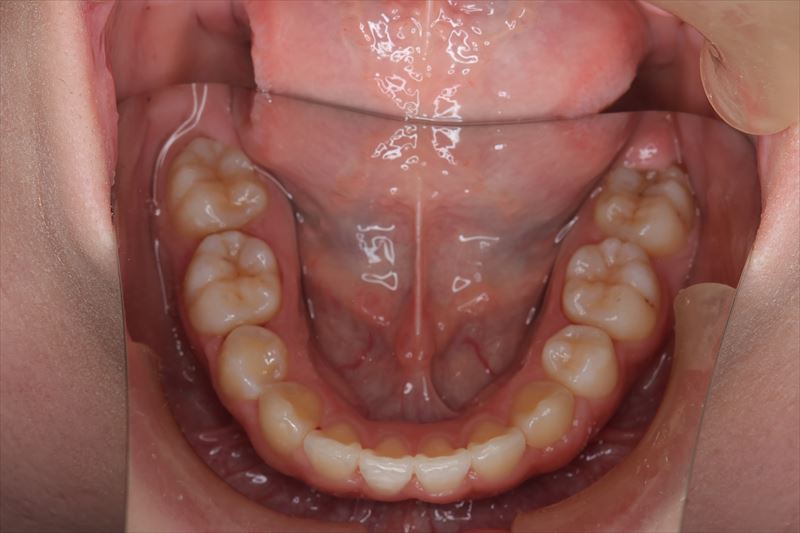

治療前

- 症状

- 叢生、口唇の突出

- 上顎両側4番、下顎右側5番、下顎左側4番抜歯

- 口唇の突出を気にされて来院いたしました。Eラインより口唇の突出、オトガイ部の緊張を認めました。アンカースクリューを用いて前歯の牽引を行うことによって良好な側貌となりました。治療途中で遠方に引っ越されたため来院が困難となり治療期間が延びてしまいましたが、患者様のご協力もあり無事に治療を終えることができました。